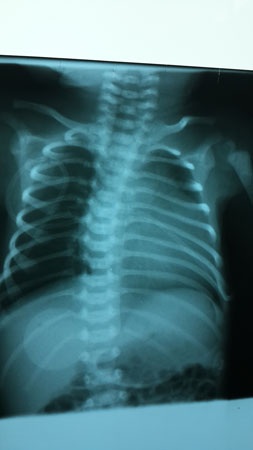

Hình ảnh X-quang của bé Duyệt trước khi phẫu thuật

Hình ảnh siêu âm của bé Duyệt trước khi phẫu thuật

và sau khi được cấy máy tạo nhịp tim